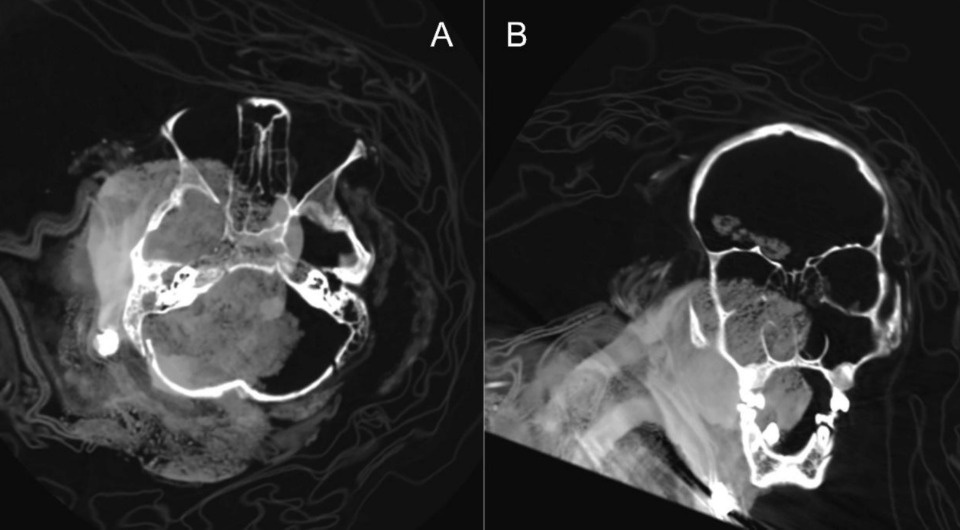

Палеопатологи обследовали с помощью компьютерной томографии мумифицированные останки четырех детей, которых около пяти веков назад инки принесли в жертву на вулканах, расположенных в Перу. Анализ снимков показал, что не все отобранные для жестокого ритуала дети были идеально здоровы, а перед смертью как минимум часть из них получила травмы головы. Кроме того, ученые заметили, что с останками одного ребенка, по-видимому, спустя какое-то время после смерти люди проводили дополнительные манипуляции, которые, возможно, были направлены на то, чтобы оставленное на горе тело лучше выглядело и сохранилось. Об этом сообщается в статье, опубликованной в Journal of Archaeological Science: Reports.